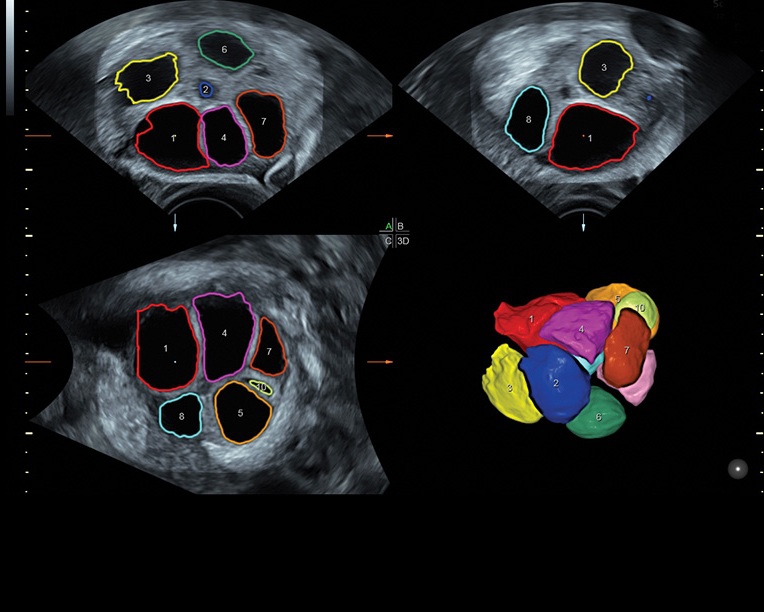

Ультразвуковая платформа Voluson S8 представляет собой оборудование экспертного класса с передовыми возможностями и высоким уровнем автоматизации процессов. Она позволяет проводить сканирование в режимах 2D, 3D и 4D с высоким качеством изображений.

Система предназначена как для коммерческой, так и для государственной медицины, в клиниках с высокой загруженностью пациентами. Voluson S8 отлично справляется с большим объемом работы благодаря шаблонизированным отчетам и автоматизации обработки и постановки диагнозов с помощью функций SonoNT, SonoVCAD, SonoAVC и STIC. Это делает аппарат коммерчески выгодным и окупаемым в ближайшей перспективе.

• Сложные инструменты для оценки качества плода: Сканер оснащен инновационными инструментами, позволяющими проводить детальную оценку состояния плода, включая его сердечную деятельность, анатомию и кровоток.

Технологии, доступные на ультразвуковом сканере Voluson S8:

• Технология SonoRenderlive: Эта технология облегчает получение 3D/4D изображений путем автоматического изменения положения плоскости визуализации в зависимости от движений плода. Она позволяет получить реалистичные и объемные изображения, что полезно для демонстрации плода будущим родителям и для дополнительного анализа.

• Программа для исследований сердца плода с возможностью цветовых допплеровских и ангиографических исследований на основе анализа пространственно-временной корреляции изображений (STIС)

• Программное обеспечение для исследования сердца плода в режиме 3D/4D (быстрый доступ к плоскостям сканирования) по рекомендациям ISUOG